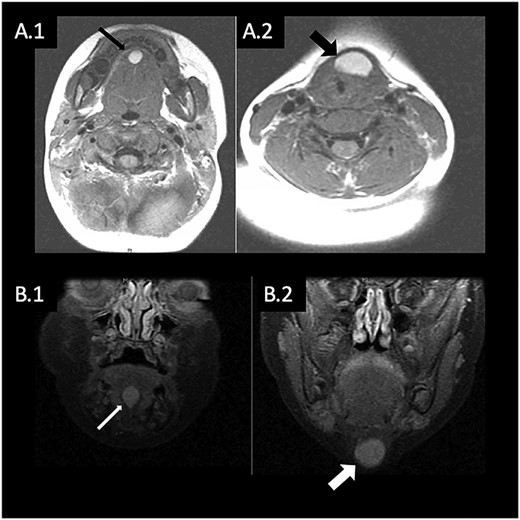

(a) Gross specimen showing multifocal cyst with thin tract. (b) Histology showing cyst lined by ciliated columnar epithelium with thyroid follicles confirming TGDC.

A transcervical approach was utilized and dissection of the midline neck mass revealed a tract extending anterior to the hyoid bone towards the FOM. Because of the close proximity with the hyoid bone, the decision was made to remove the midportion of the hyoid. Once dissection was carried through the mylohyoid, the tract was found to be in continuity with the FOM cyst. There was no evidence of a connection with the base of tongue/foramen cecum. The final specimen revealed a 3.0 × 2.5 × 1.8 cm mass with a 2 cm long tract connecting to the second 1.0 × 1.0 × 0.8 cm mass (Fig. 2a). The specimen was sent to pathology, which revealed a cystic structure with thyroid follicles, confirming the diagnosis of TGDC (Fig. 2b). At most recent follow-up with the patient’s pediatrician 1 year postoperatively, physical exam of the mouth and neck was normal with no evidence of recurrence.